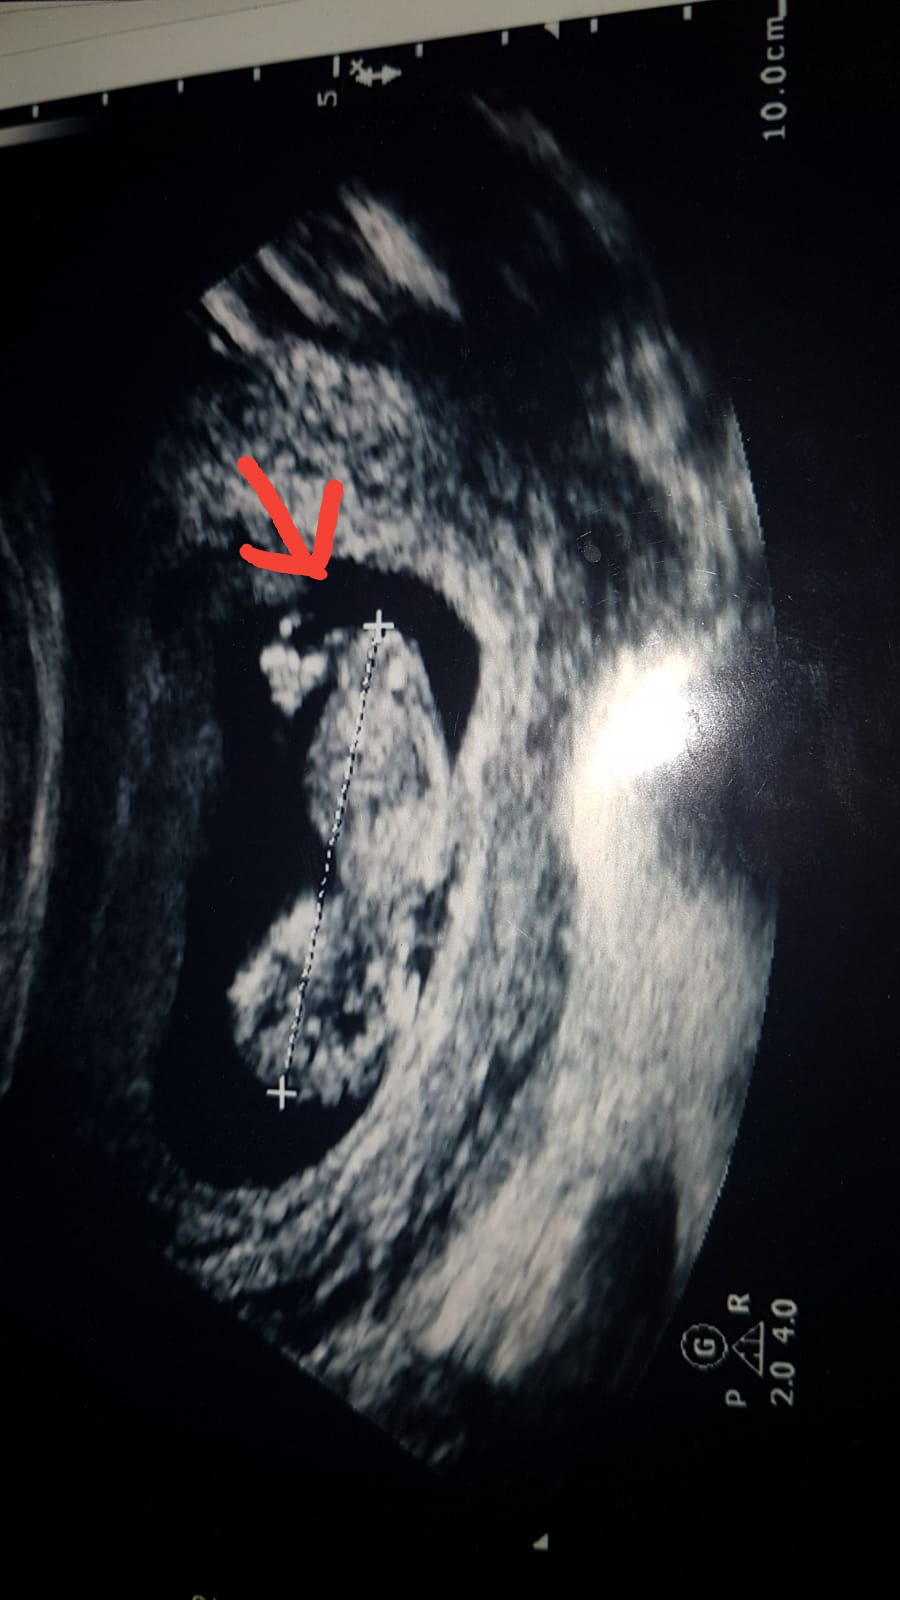

Benimde bakarmısınız lütfen doktor erkek dedi sonra gene erkek dedi kıza benziyor dedi yok yok erkek dedi bende sasrdm

aslinda merak ettigim su okla gosterdigim yer.12 haftalik bebegin genital organlari bu haftada tam olusmus olabilir mi ve ultrasonda bu kadar net gorulebilir mi ki doktorum cok net bir sekilde erkek demisti

Bebeğin cinsiyeti oluştuğu andan itibaren bellidir aslında ama bu en erken nub teoirisi ile 12. haftada öğrenilebilir. Bu haftalarda yanılma payı yüksektir bu nedenle benzer paylaşımların hepsine bebeğin cinsiyetinin 17-19-20 haftalarda net şekilde öğrenilebileceği notunu düşüyoruz.